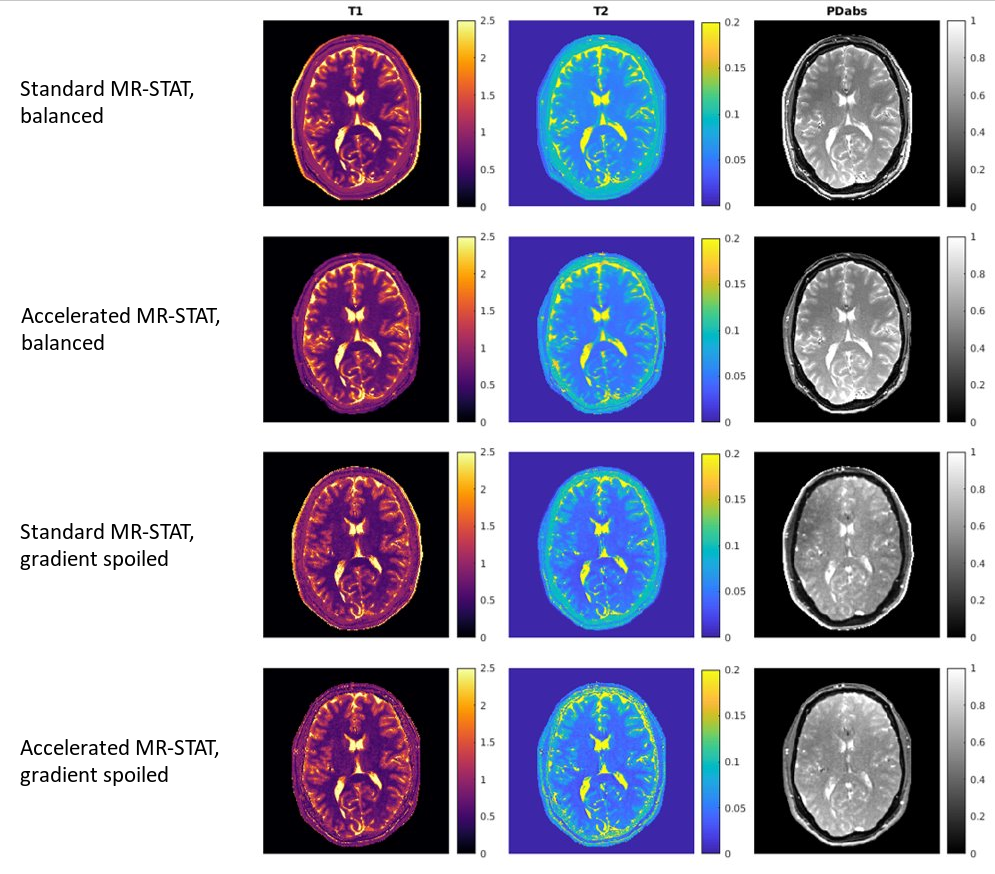

Figure 5: Comparison between standard and accelerated MR-STAT reconstructions. Quantitative maps including $$$T_1$$$, $$$T_2$$$ and PD from both balanced (scan time 10.3s) and gradient spoiled (scan time 9.8s) sequences are shown. The image size is 224x224 with resolution of 1.0x1.0x3.0mm$$$^3$$$. Four SVD compressed virtual-coil data are used for reconstruction.